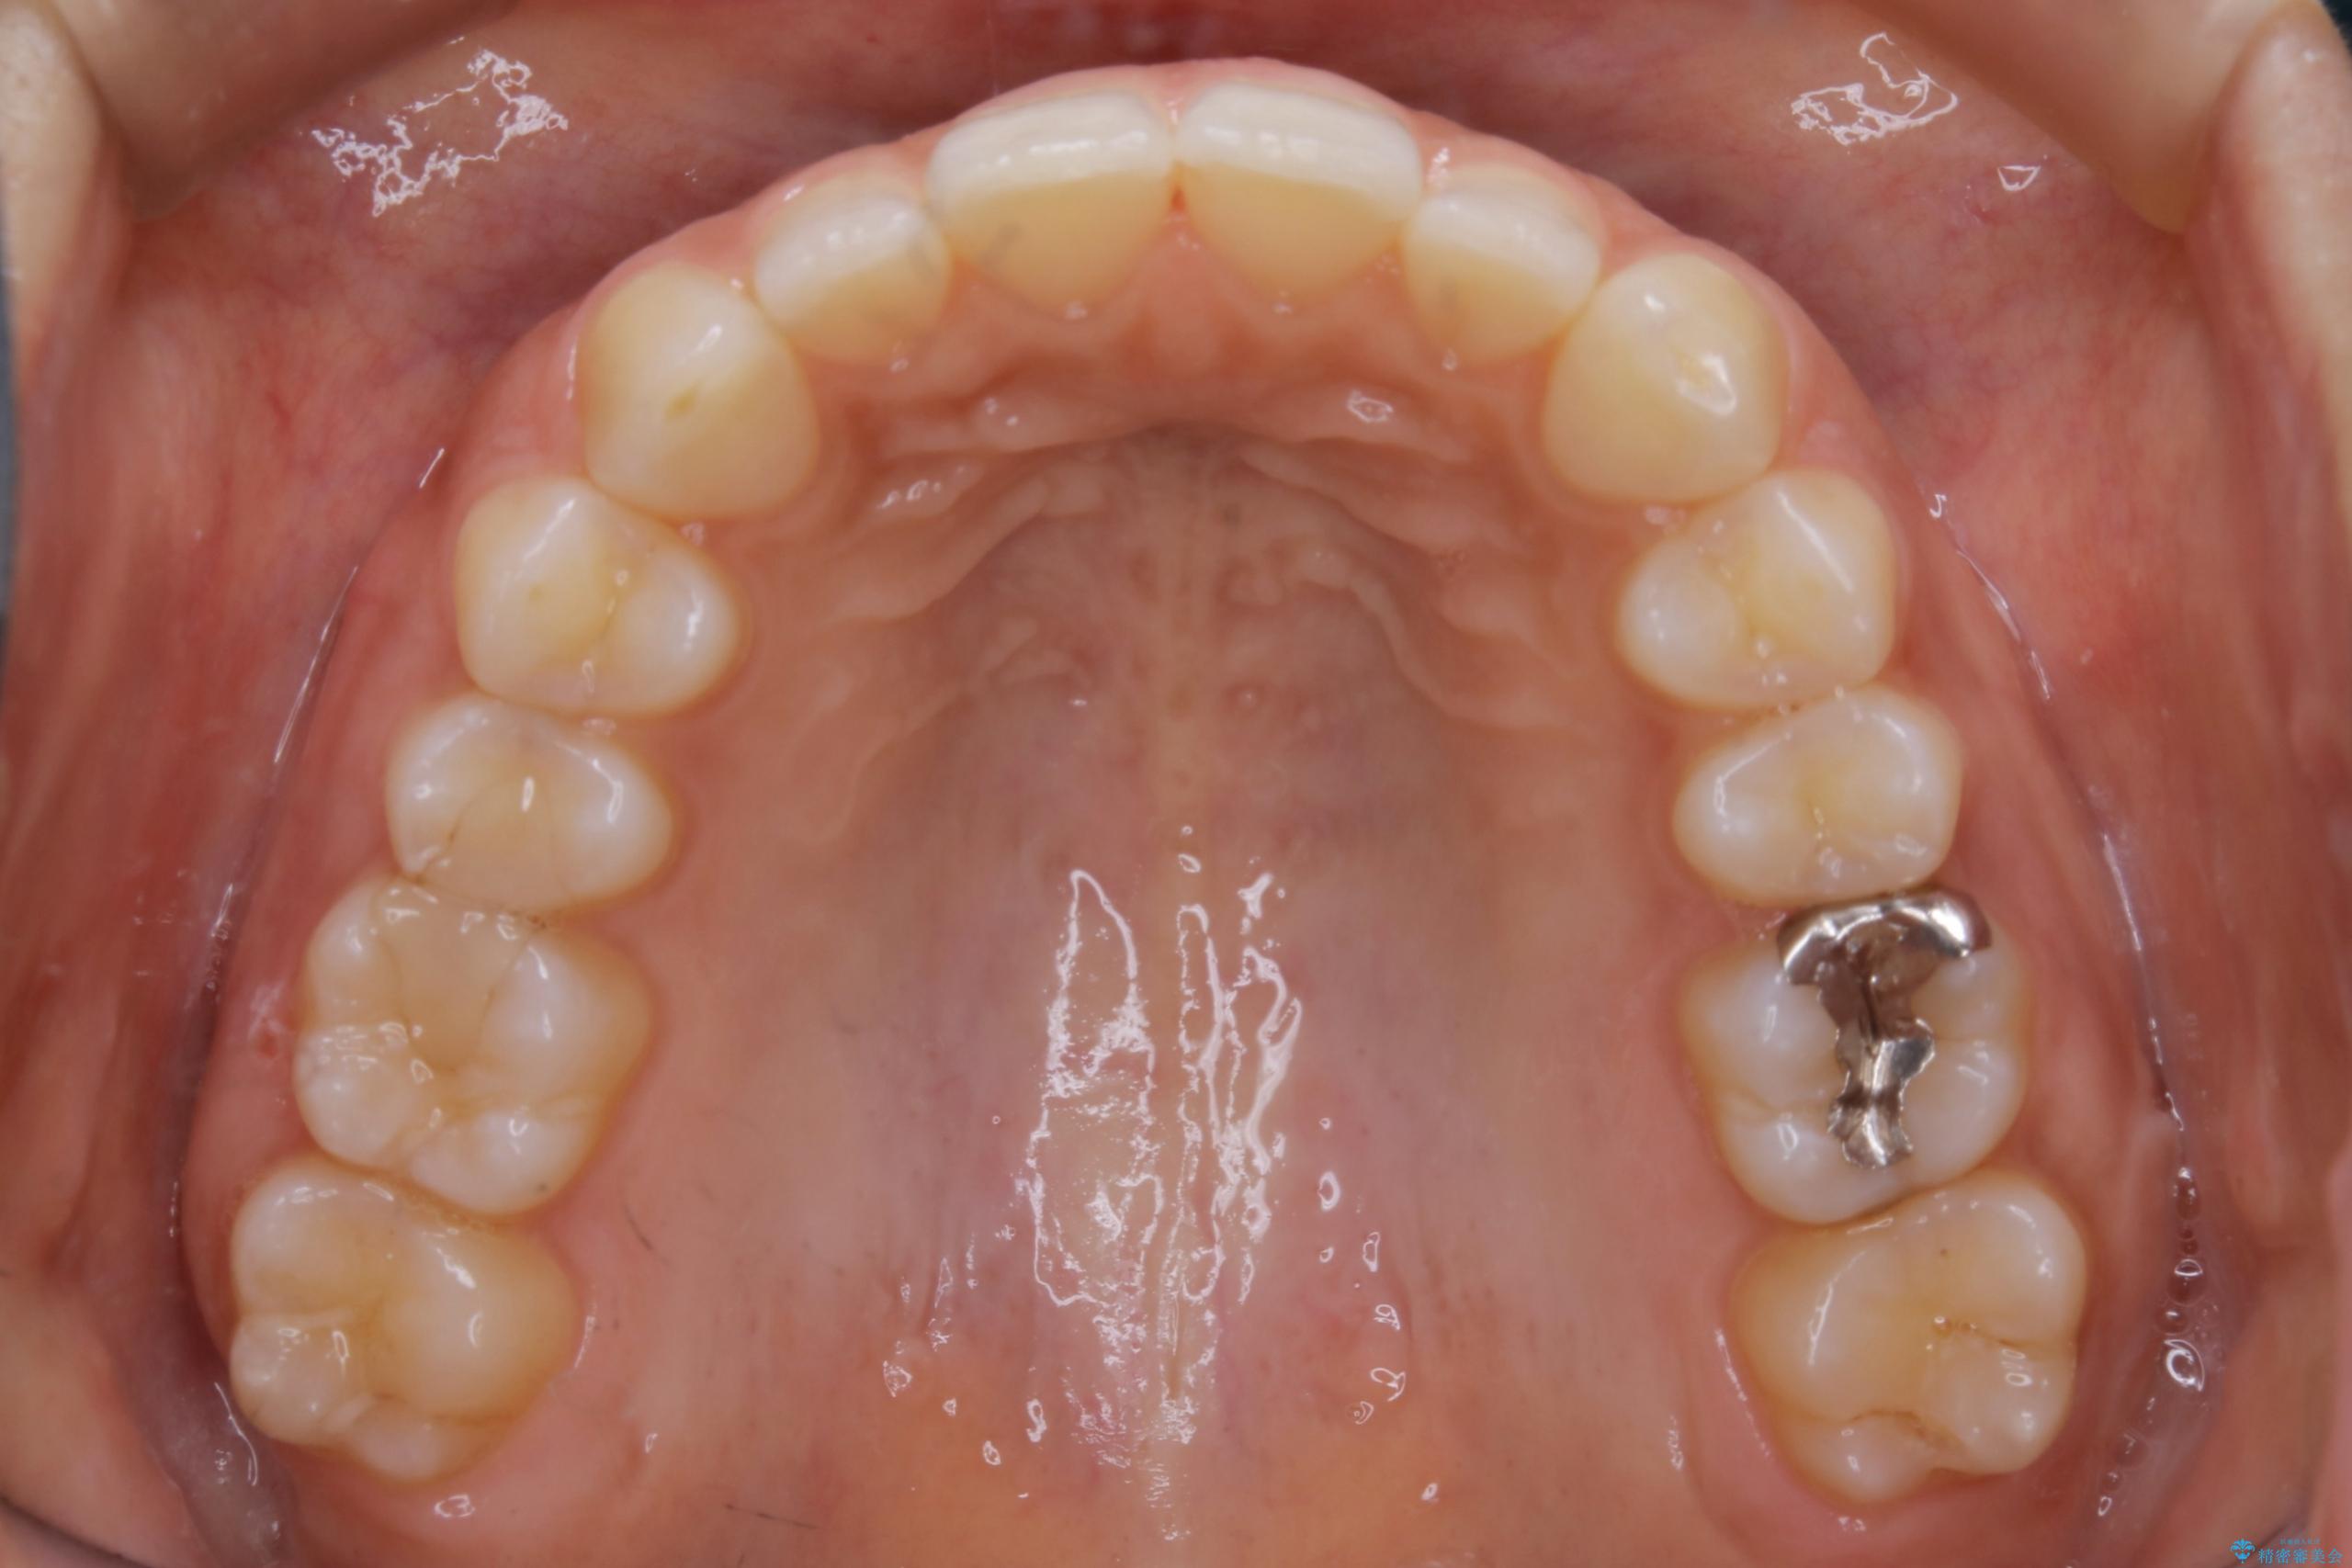

20代 女性 ゴムかけを併用し噛み合わせを改善!インビザライン矯正

気になるガタツキと噛み合わせを改善したいとご来院されました。

下の歯列よりも上の歯列が前に出ている状態を治すため、マウスピース矯正に加え、患者様にゴムかけのご協力をいただきました。その結果、ガタつきが改善し、上下の噛み合わせが適切な位置で合うようになりました。

歯列弓の拡大

歯並びが悪くなる原因の一つに「歯列弓の狭窄」というものがあります。

奥歯や前歯が内側(舌側)に倒れ込んでしまったり、歯が生えてくる位置が内側になってしまうことにより歯並びのアーチが狭くなってしまうことを言います。

このような場合、歯並びのアーチを拡大してあげるだけでもガタつきを無くすためのスペースがかなり作れることがあります。